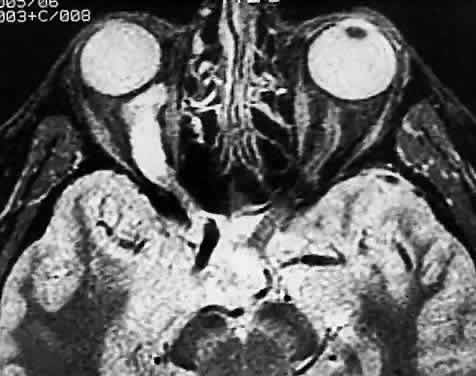

The optic nerve is affected in some manner in 1% to 5% of patients with sarcoidosis and is the second most frequently involved cranial nerve—the facial nerve being the most common.67,68 Rarely, sarcoidosis may present as tumefactive enlargement of the optic nerve without evidence of systemic disease. Most cases are misdiagnosed initially as meningioma or orbital pseudotumor (Figs. 50 and 51).67,69

Fig. 50. Bilateral thickening of the optic nerve and sheaths due to sarcoidosis. Computed tomography.